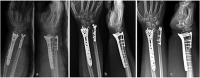

A peri-implant fracture near the volar plate of distal radius represent a very rare injury. The main factor of this lesion is high energy trauma on the wrist. We report a case of a 61-year-old woman with a peri-implant fracture located just proximally to the plate and a fracture of the ulnar head that occurred after a simple fall. The patient was surgically treated by plate and screws removal. The fracture was fixed using a longer volar plate for the radial fracture and a plate for the head ulnar fracture. Different factors such as osteoporosis, BMI and screw position could influence the fracture pattern. However, considering growing use of plates for distal radius fracture fixation, the frequency of these kind of fracture will probably increase.